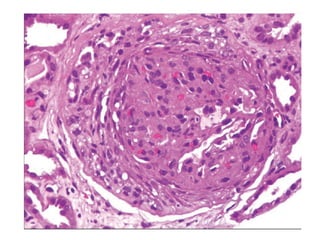

MECHANISM AND EXTENT OF INJURY

• The pathological responses of glomerulus injury involves -

hypercellurarity

-glomerular basement membrane thickening and

-hyalinosis and sclerosis.

• Hypercellularity involves -cellular proliferation

&leukocyte infiltration.

- crescent formation.

• GBM thickening-lamina densa dublication

-immune complex deposition

-increased protein content of the GBM

and electron dense materials.

• hyalinosis

-leakage of plasma proteins from the injured endothelium

or capillaries with deposition of homogeneous and

oesinophilic materials in the glomeruli.

• Sclerosis

-deposition of extracellular collageneous matrix.